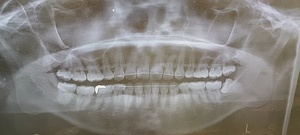

どうやって診断される?|検査・受診の流れを解説

歯科・口腔外科での診察方法

医師の視診で典型的な白斑や網目状の模様が観察されれば、口腔扁平苔癬と仮診断されることが多いです。

【がん化の危険性】口腔扁平苔癬は口腔がんになる可能性がある?

がん化リスクはどのくらい?

口腔扁平苔癬のがん化率は文献によって異なりますが、0.5~2%程度と報告されています。長期・重症病変や潰瘍形成のある例では注意が必要です。

観察・経過観察が必要な理由

病変ががん化している兆し(硬さ、色の変化、潰瘍化)が現れる場合があるので、定期的な診察と写真記録によるモニタリングが推奨されます。また自己チェック法として、鏡を使用して病変の変化を確認する習慣も有効です。